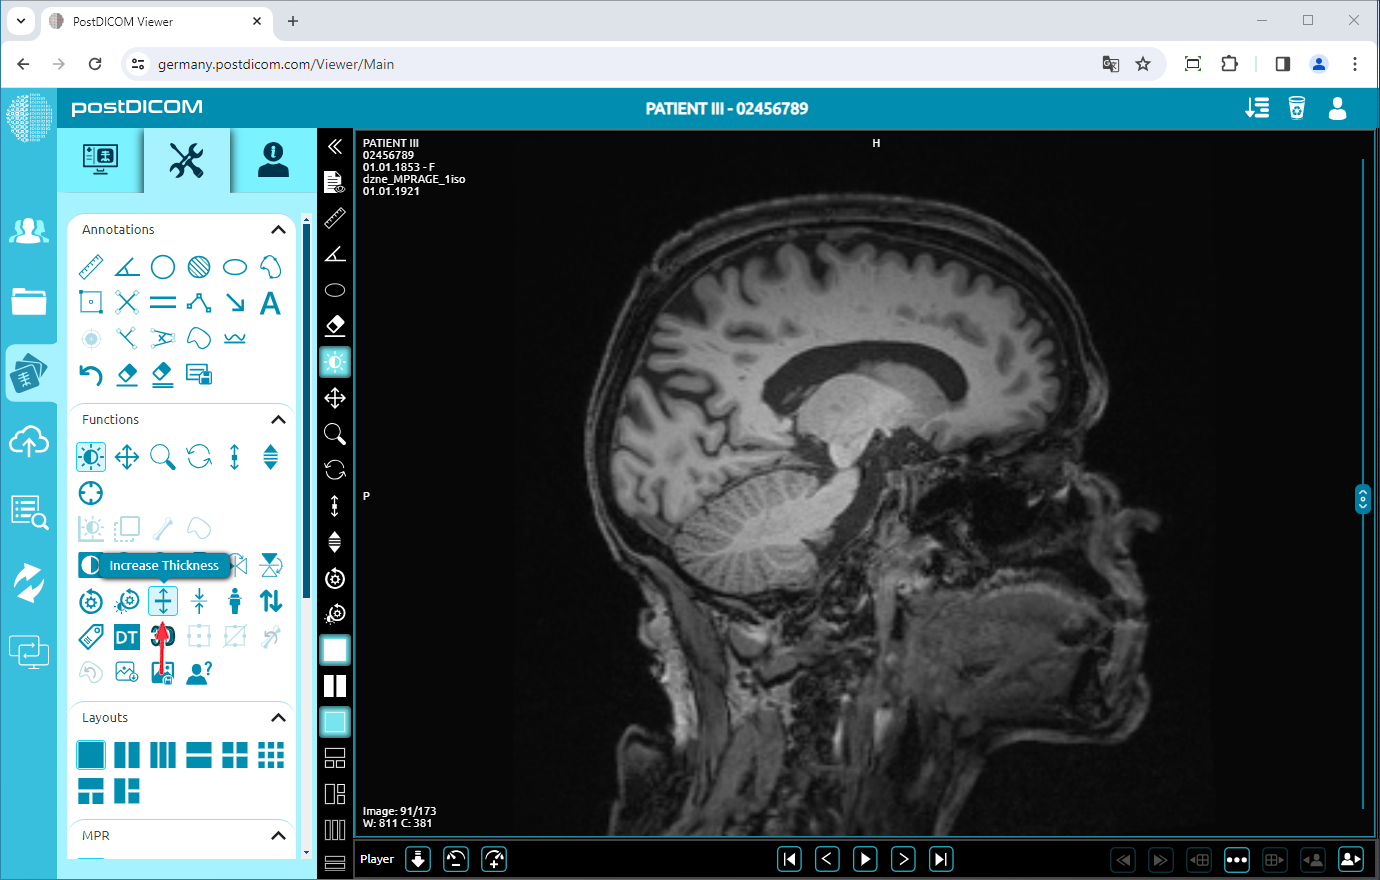

Increase/Decrease Thickness

Click on the “Increase Thickness” icon on the left side of the page to increase the thickness of the image by one level.

Once you have clicked, you will see one level-thickened image on the viewport. The more you click, the image will be thicker